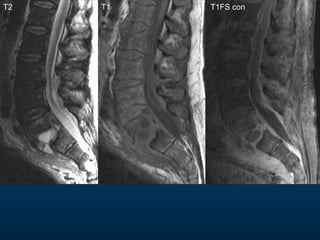

T2 T1 T1FS con

•  62 yearold male •  Severe low back pain of rapid onset •  Febrile and unwell •  4 weeks ago underwent abdominal surgery for perforated diverticulitis MRI